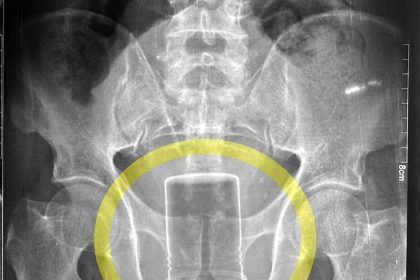

Farmer gets can of insecticide stuck up his bum for SIX weeks

A man lived with an insecticide can stuck in his rectum for…